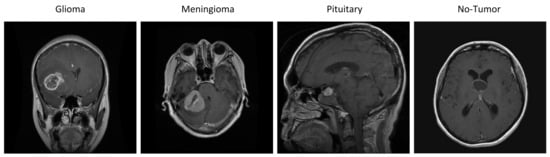

- This study presents a novel approach that combines hybrid attention with convolution neural networks to improve the efficiency of diagnosing glioma, meningioma, pituitary, and no-tumor cases.